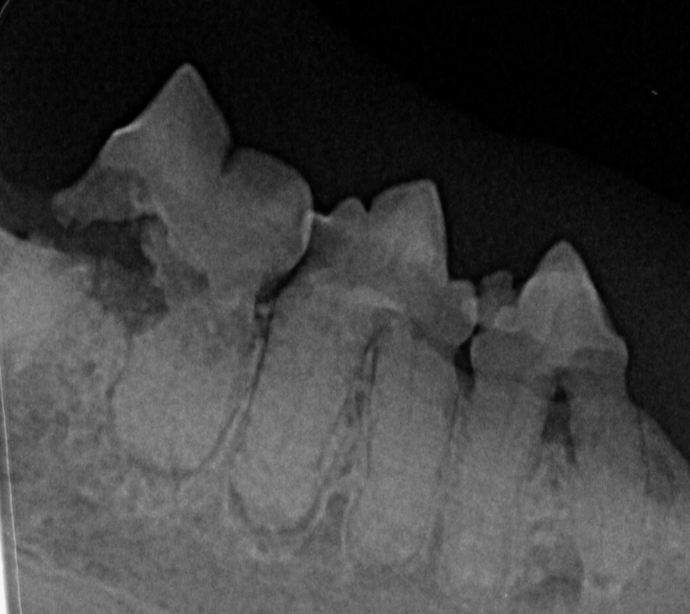

Photo 3 - abgebauter Knochen

Photo 5 - abgebauter KnochenPhoto 4 - abgebauter Knochen

Auf den 3 Bildern sieht man jeweils wie der Knochen sich aufgrund einer Entzündung abgebaut hat.

Werden die Zähne geröntgt, können wir sehen was genau mit dem Knochen durch die Entzündung passiert ist und welcher Zahn gezogen werden muss. Ohne Röntgen sieht man nur die Spitze des Eisberges.